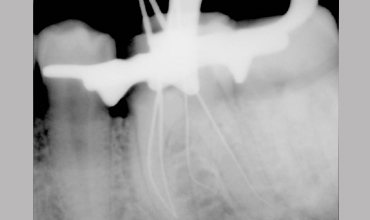

Management Of Radix Entomolaris In Mandibular First Molar